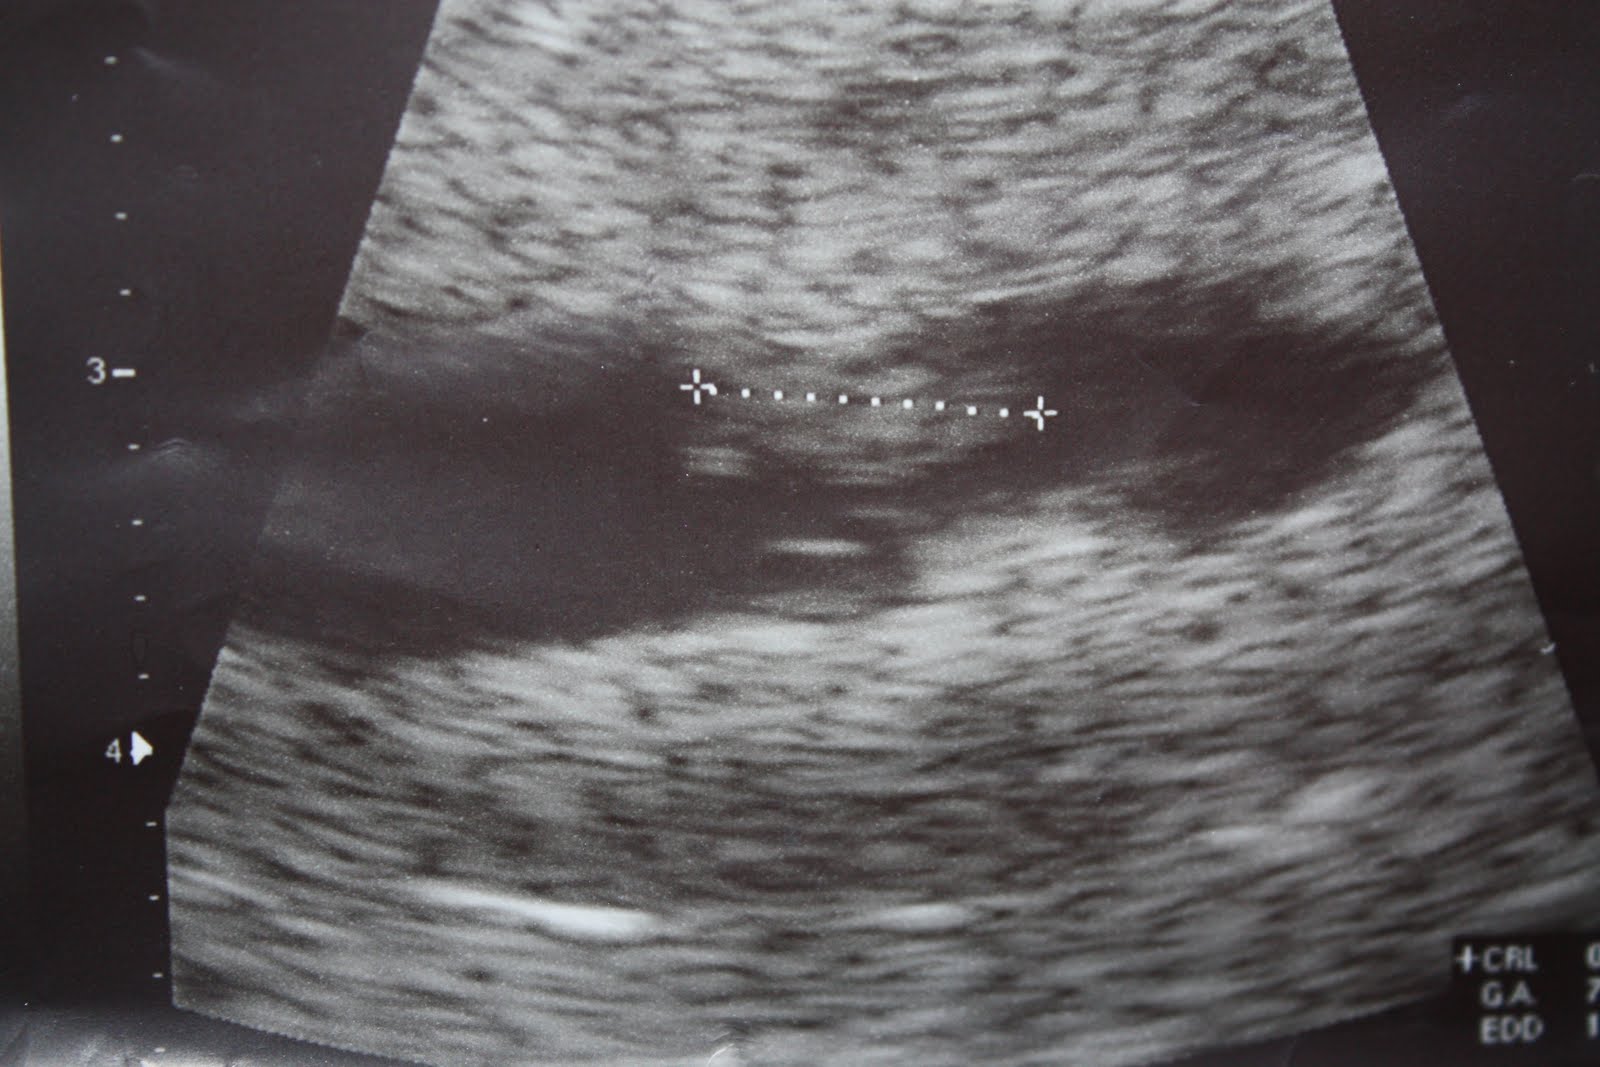

What a gift you are indeed! As your Nana said, it’s like God handed you to us on a silver platter. Our whole family is still just beaming at the news of your expected arrival around Thanksgiving! We will have so much to be thankful for! Right now you are only 7 weeks and about the size of a blueberry. Today we got to see you for the first time and hear your precious heartbeat, what a wonderful birthday gift for your daddy! You were measuring exactly to the size you should be for your due date, November 23rd. Dr. Mascarro said everything looked just perfect, very reassuring words for us all.